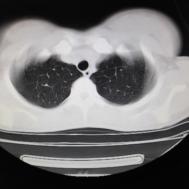

性别:女,年龄:26岁,低热,轻微胸痛,支原体阳性

[影像描述]

两肺内及胸膜下多发斑片状高密度影,部分病灶密度较淡,部分实变,边缘可见渗出改变。